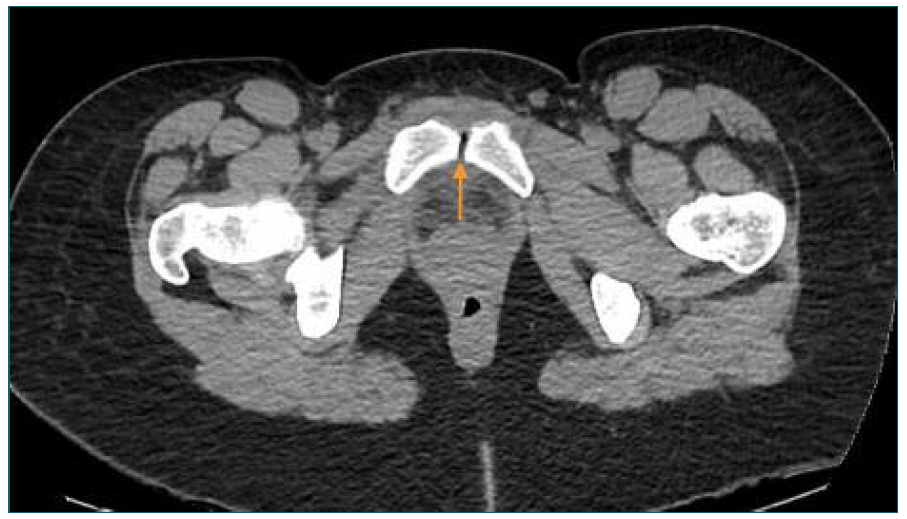

For this reason, a computed tomography (CT) was performed and showed pre-pubic soft tissues higher density and intra-articular air in the symphysis pubis (Figure 1), which led to suspicion of an osteitis. A magnetic resonance imaging (MRI) confirmed the diagnosis by showing hyperintense T2 signal and cortical irregularities on the articular surface associated with few intra-articular fluid and densifications of the soft tissues (Figures 2 and 3). At the same time, blood cultures were positive for Streptoccocus Anginosus and a puerperal osteomyelitis pubis was assumed. Antibiotic therapy was changed to intravenous benzylpenicillin (24 million Units per day), according to the antibiogram. Considering the high diagnostic certainty, based on clinical and imagological features, and technical difficulties, an aspirative biopsy was not performed. In consideration to Streptoccocus Anginosus found on blood cultures, the patient was submitted to an echocardiogram that excluded any sign of endocarditis.

Figure 1 Pelvic CT scan. CT scan demonstrating intra-articular air and high density of soft tissues.